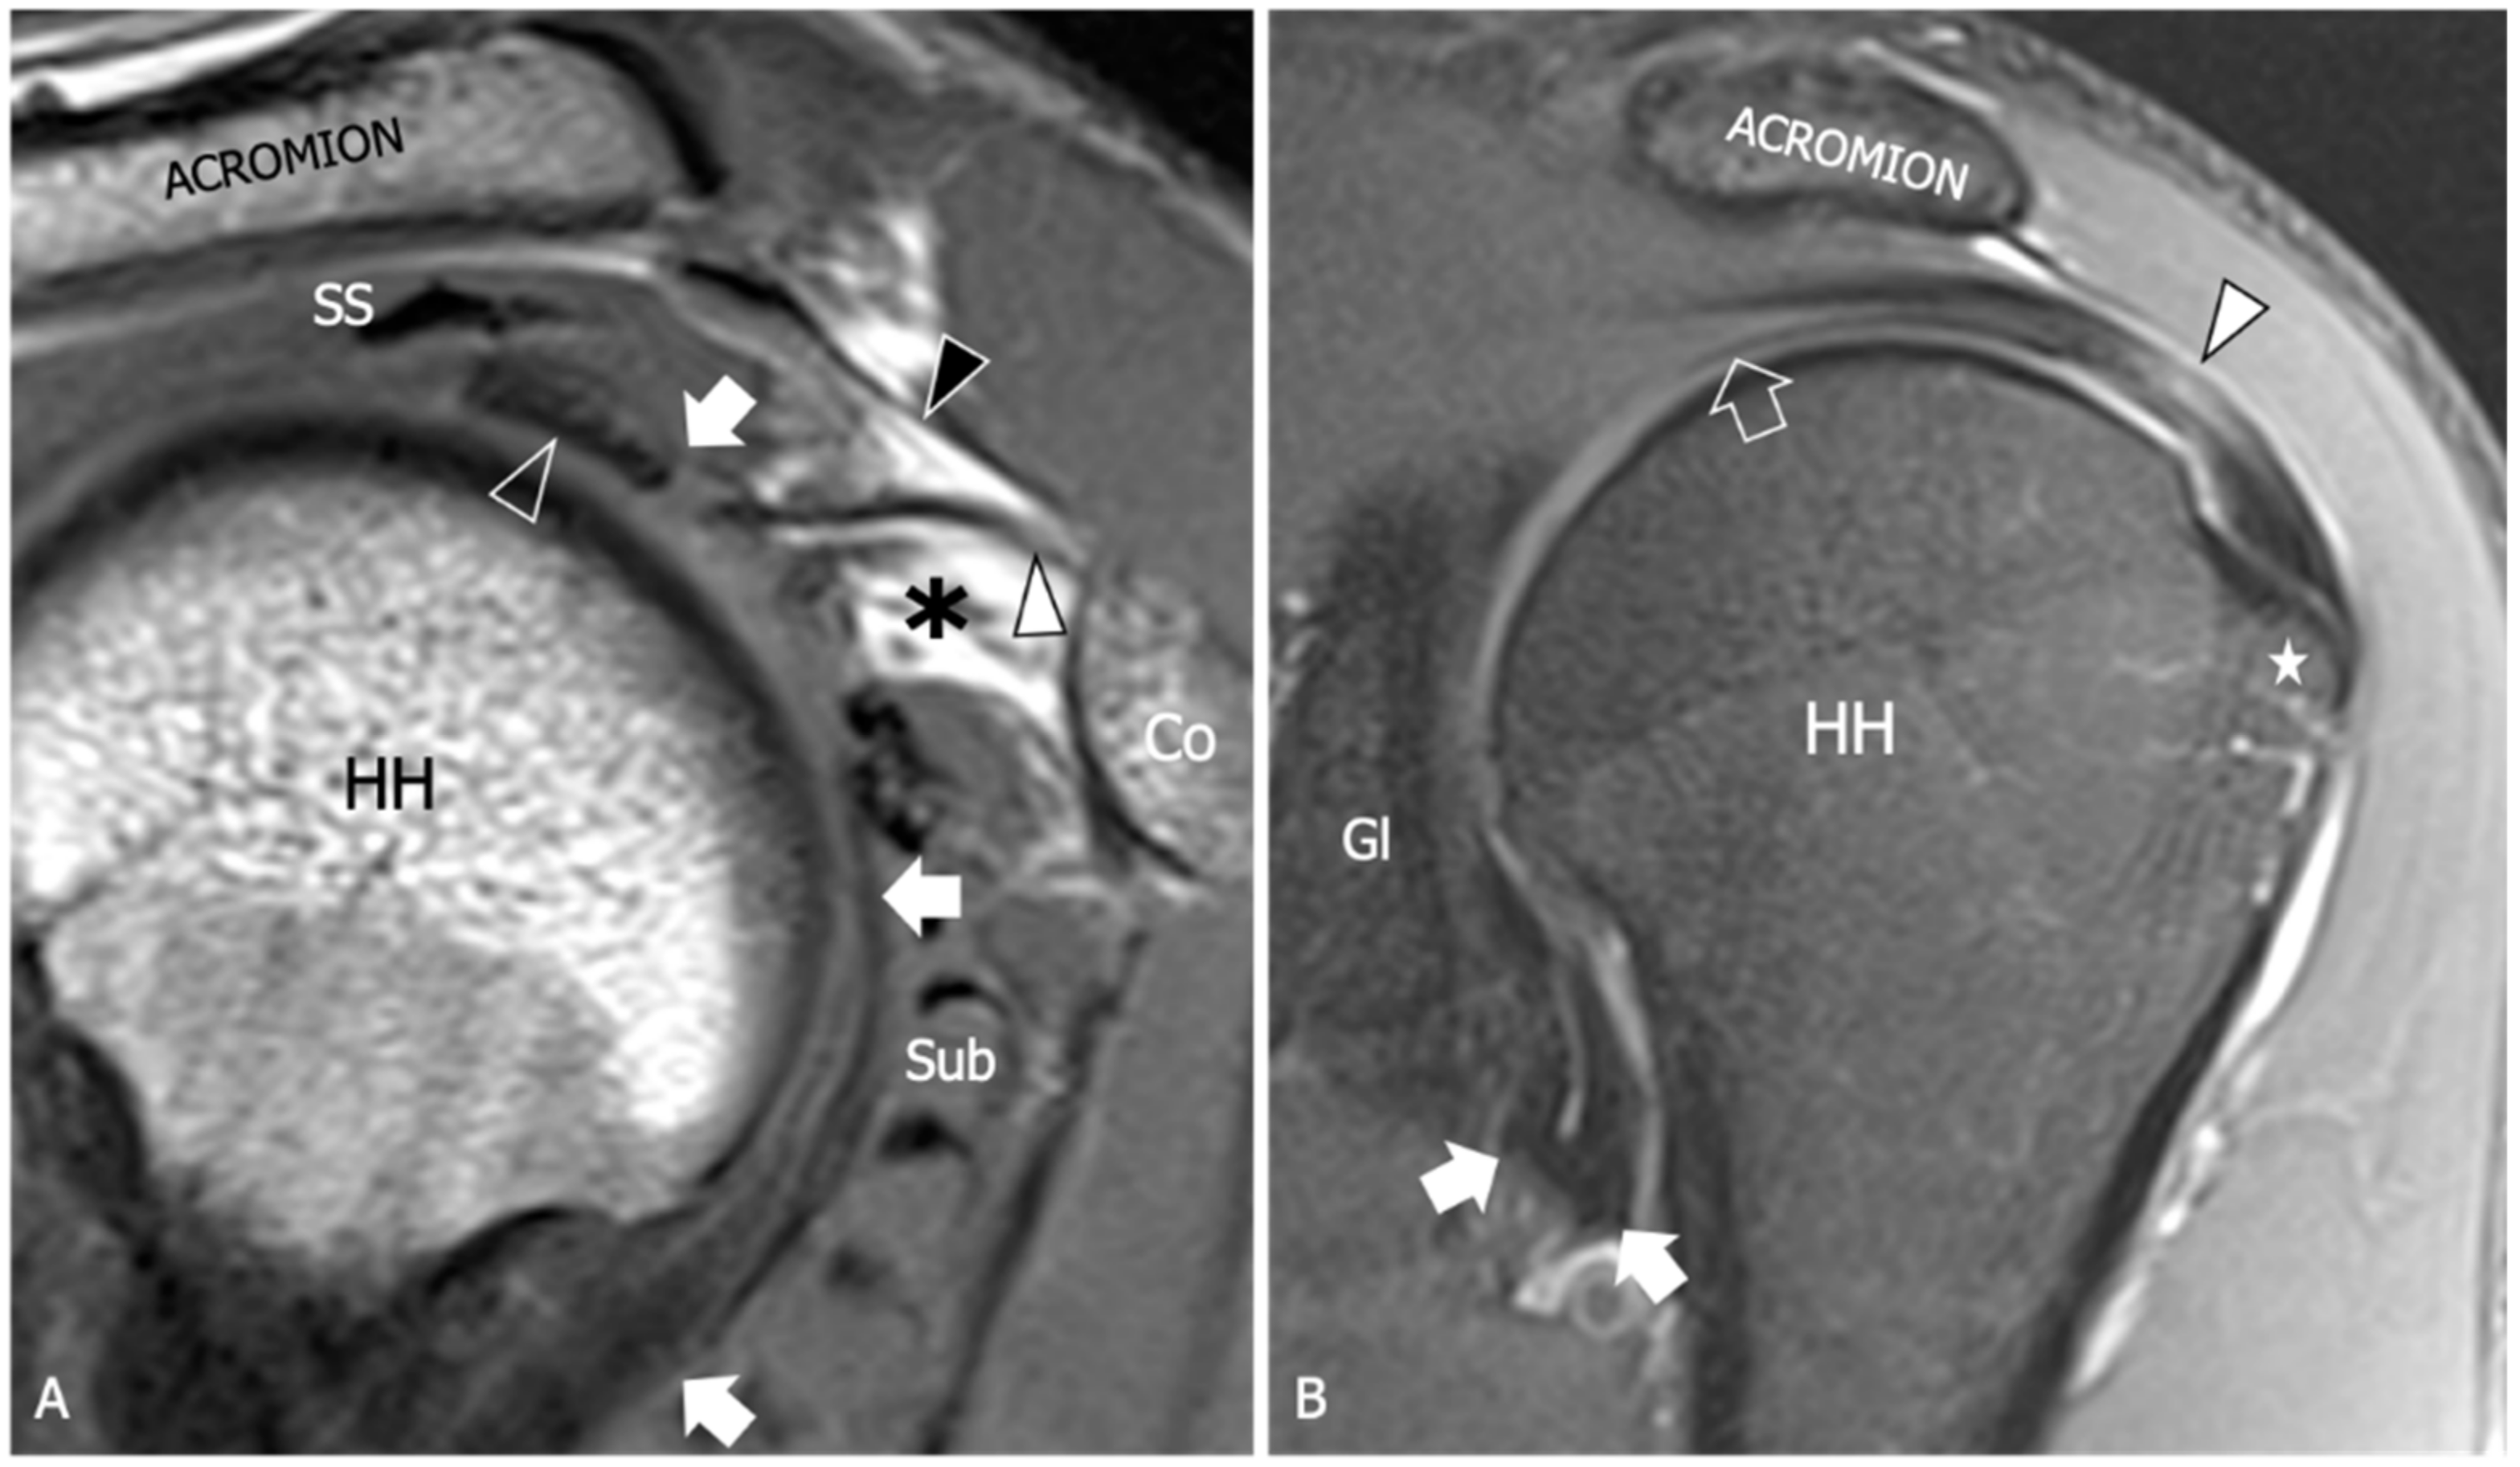

| Thickening of the coracohumeral ligament, fat obliteration of the rotator interval, hyperintensity and thickening of the inferior glenohumeral ligament, and contrast enhancement of the axillary joint capsule and the rotator interval are the most accurate signs of AC. The sensitivity and specificity of inferior glenohumeral thickening detected on conventional MRI are not significantly different from those detected on direct MR Arthrogram: consequently, the non-arthrogram MRI is recommended for AC diagnosis. | [53] |

| The rotator interval capsule thickness ≥7 mm has a specificity of 86% and a sensitivity of 64% for AC diagnosis. A coracohumeral ligament thickness ≥4 mm has high specificity (95%) but lower sensitivity (59%) for AC. Obliteration of the triangular fat pad inferior to the coracohumeral ligament has high specificity (100%) and poor sensitivity (32%). | [54] |

| Thickening of the rotator interval over 6 mm on sagittal oblique proton-density images may correlate with the patient’s range of rotational motion. An axillary recess capsule thickness of more than 4.5 mm measured on T1 oblique coronal images demonstrated the greatest diagnostic accuracy for AC diagnosis, with a sensitivity, specificity, and overall accuracy of 91%, 90%, and 90%, respectively. | [55] |

| Obliteration of the subcoracoid fat triangle has been more frequently observed in early stages of AC. Capsule thickness and hyperintensity on proton density sequence correlate with clinical stages. | [56] |

| Hyperintensity in the axillary pouch/inferior glenohumeral ligament complex on MRI using non-arthrography T2-weighted fat-suppressed sequences demonstrated high sensitivity (85.3–88.2%) and specificity (88.2%) and low variability among different observers with a kappa value of 0.85. | [57] |

| An axillary recess capsule thicker than 4 mm on T1 oblique coronal MR images suggests a diagnosis of AC with a sensitivity of 70% and a specificity of 95%. | [58] |

| A positive linear correlation is demonstrated between the grade of axillary recess capsule enhancement, the thickness of the joint capsule, and the intensity of pain in individuals with AC. No association was observed between the aforementioned parameters and the severity of range of motion limitation. | [59] |

| No differences in the accuracy of AC diagnosis emerged between conventional MRI and gadolinium-enhanced MRI despite the intravenous administration of contrast agent demonstrated to have some effects in increasing the reader’s confidence in measuring the joint capsule. | [60] |